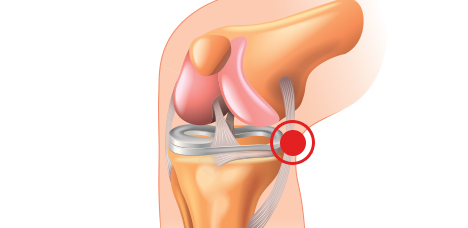

슬개건염

무릎 아래쪽 힘줄에 염증이 발생한 질환

거위발 건염

무릎 안쪽 힘줄에 염증이 발생한 질환

장경인대염

무릎 바깥쪽에 염증이 발생한 질환

무릎 관절염

슬개골연화증, 관절염 등으로 인해 통증이 발생